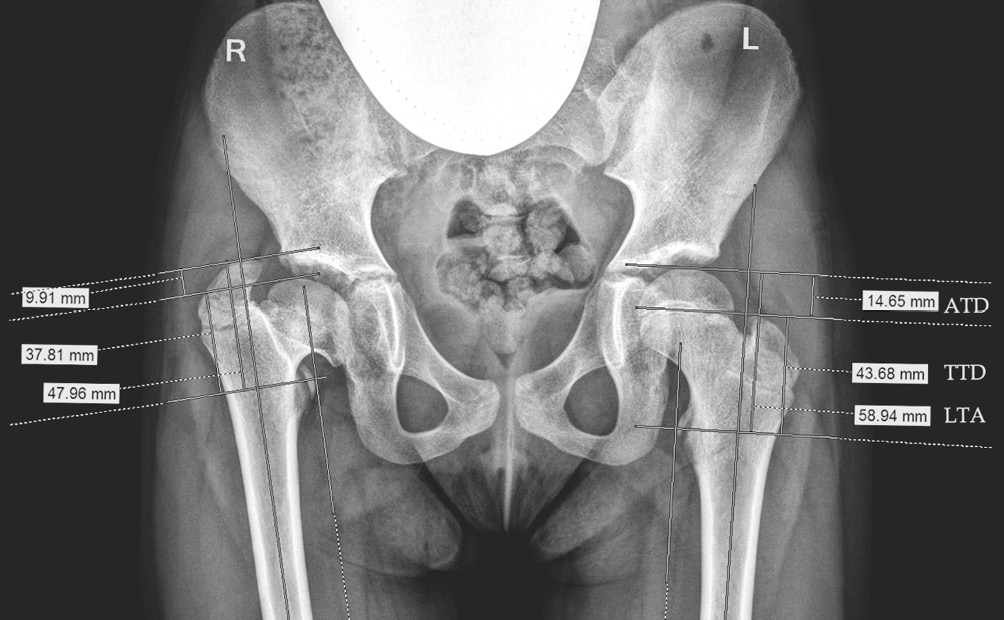

In all 350 patients observed, the ratio of the greater trochanter apex to the center of the femoral head was in the pathological range, which served as the main criterion for inclusion in the study. For a detailed analysis of the ongoing anatomical changes, we studied additional indicators characterizing the ratio of the femoral head and the greater trochanter in the frontal view in 56 examined patients (112 hip joints). The development of 48 (42.9%) joints in them was normal (with unilateral lesion) (Fig. 1).

These indicators included the following:

1) articulotrochanteric distance (ATD) — the distance from the apex of the greater trochanter to the upper pole of the femoral head (mm);

2) trochanter-to-trochanter distance (TTD) — the distance from the apex of the greater trochanter to the middle of the lesser trochanter along a line parallel to the anatomical axis of the femur. This indicator reflects the growth of the greater trochanter and does not depend on the growth of the epiphysis;

3) lesser trochanter-to-articular surface distance (LTA) — reflects the growth of the epiphysis and the femoral neck and does not depend on the growth of the greater trochanter.

Fig. 1. Indicators characterizing the ratio of the femoral head and the greater trochanter in the frontal view (Mccarthy J.J., Weiner D.S., 2008, as amended) [12]. ATD — articulotrochanteric distance; LTA — lesser trochanter-to-articular surface distance; TTD — trochanter-to-trochanter distance

Despite the diversity of the diseases in these patients, the radiological abnormalities were similar; in particular, the ratios of the greater trochanter apex to the center of the femoral head were in the pathological range. In view of these findings, we examined in more detail the indices characterizing changes in the growth of the greater trochanter in relation to the femoral head and neck. To clarify the dynamics of changes in the radiological parameters of the proximal femur, we analyzed digital radiographs of 56 patients (112 joints), performed with proper scaling and with the use of a calibrator to obtain the correct data (Fig. 6).

Fig. 6. An example of radiographic analysis of indicators that characterize changes in the position of the greater trochanter in relation to the femoral head and neck. ATD — articulotrochanteric distance; LTA — lesser trochanter-to-articular surface distance; TTD — trochanter-to-trochanter distance